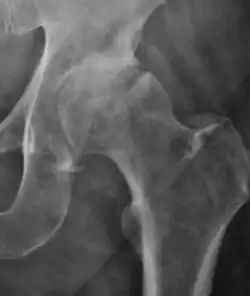

Plain radiography allows us to categorize the hip as normal or dysplastic or with impingement signs (pincer, cam, or a combination of both). Besides these, pathologic processes like osteoarthritis, inflammatory diseases, infection, or tumors can also be identified (Figure 1).[1]

Figure 1.

-

Radiography in normal hip -

X-ray in pincer impingement type of hip dysplasia -

X-ray of cam -

Hip in osteoarthritis -

Septic arthritis

X-ray in pediatrics